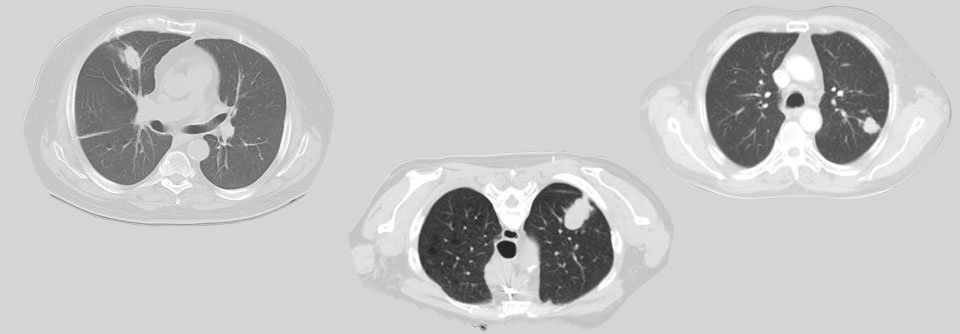

Lungenkrebsscreening: Wie geht es nach dem auffälligen Befund diagnostisch weiter?

Jetzt, da das Lungenkrebsscreening für Risikogruppen vor der Tür steht, stellt sich die Frage: Wer darf eigentlich ran an die abzuklärenden Rundherde?…

Pneumologie , Onkologie und Hämatologie DGIM 2021

Lungenkrebs-Mortalität senken – kommt bald das CT-Screening?

Ein mögliches Lungenkarzinom-Screening in Deutschland kommt ins Rollen. Derzeit läuft eine Bewertung durch das Bundesamt für Strahlenschutz. Fällt…

Onkologie und Hämatologie DGIM 2021